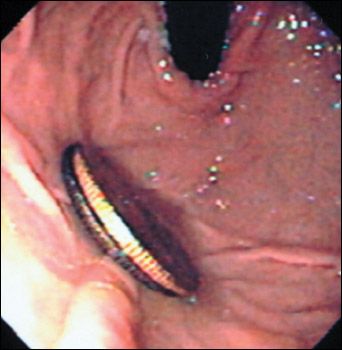

Figure 1 – The swallowed coins as seen on endoscopy (the darker coin is the Canadian quarter).

Based on a history of a similar rash in the periumbilical area after exposure to a nickel-containing jeans stud, and the lack of constitutional symptoms, it is most likely that this patient's rash is an allergic reaction to the nickel component of the coins he swallowed. The quarters were removed endoscopically (Figures 1and 2). One of the coins was a Canadian quarter, composed of 100% nickel without plating.1 The other was a US quarter, composed of a copper-nickel alloy.2 During endoscopy, it was noted that gastric mucosa in contact with the quarters had eroded. Therefore, a 1-week course of ranitidine was started.

Figure 2 – The coins after removal show the changes in the Canadian quarter.